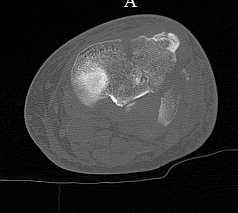

скан, который, на мой взгляд наиболее интересен

Серия КТ сканов в аппарате